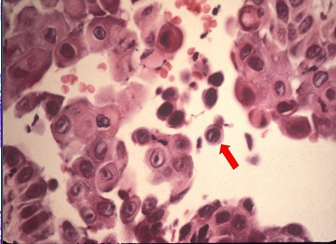

What is acantholysis in Pemphigus Vulgaris?

What are Tzank cells in Pemphigus Vulgaris?

Loss of attachment between the epithelial cells results in detached cells that appear rounded, present in the area of separation

Sloughing of the epithelium Ulcers in Pemphigus Vulgaris

What is the diagnosis for Pemphigus Vulgaris?

Biopsy and Direct immunofluorescence (DIF)- INTRA-EPITHELIAL separation